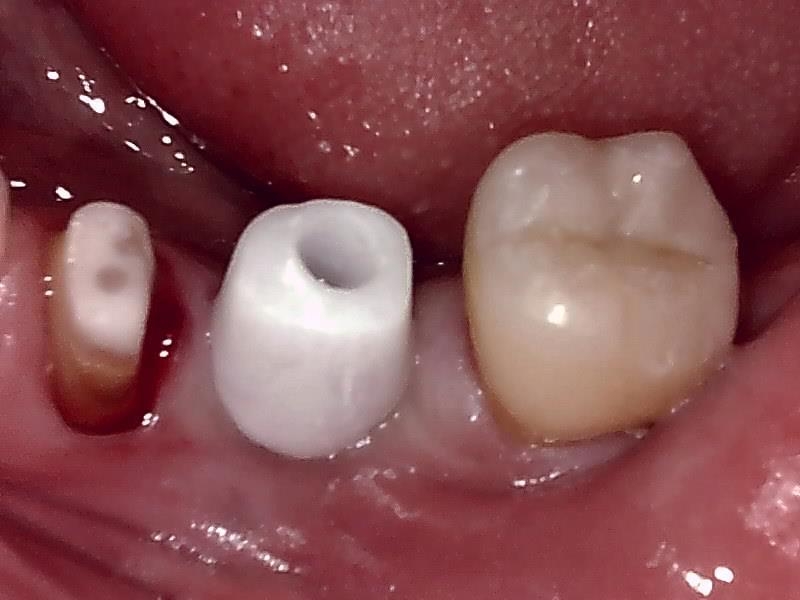

アバットメント装着 (左下)

(ジルコニアアバットメント)

歯肉の整形 (左下)とても綺麗な良い歯肉の状態です。